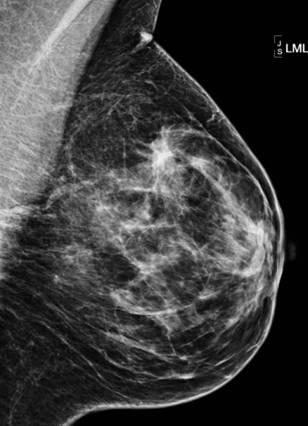

Ung thư vú

Ung thư vú - Ảnh 2

» Thông tin: Nữ giới – 55 tuổi.

» Lâm sàng: Khối tuyến vú.